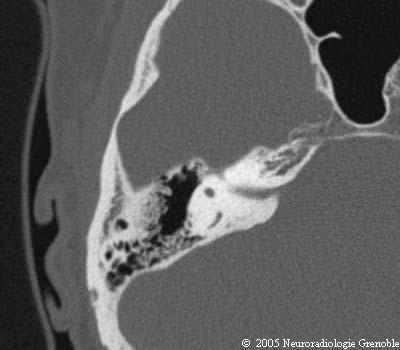

Rocher coupes TDM

Radioanatomie TDM du rocher normal

Conduit auditif interne

Canal semi-circulaire supérieur

Canal semi-circulaire postérieur

Antre